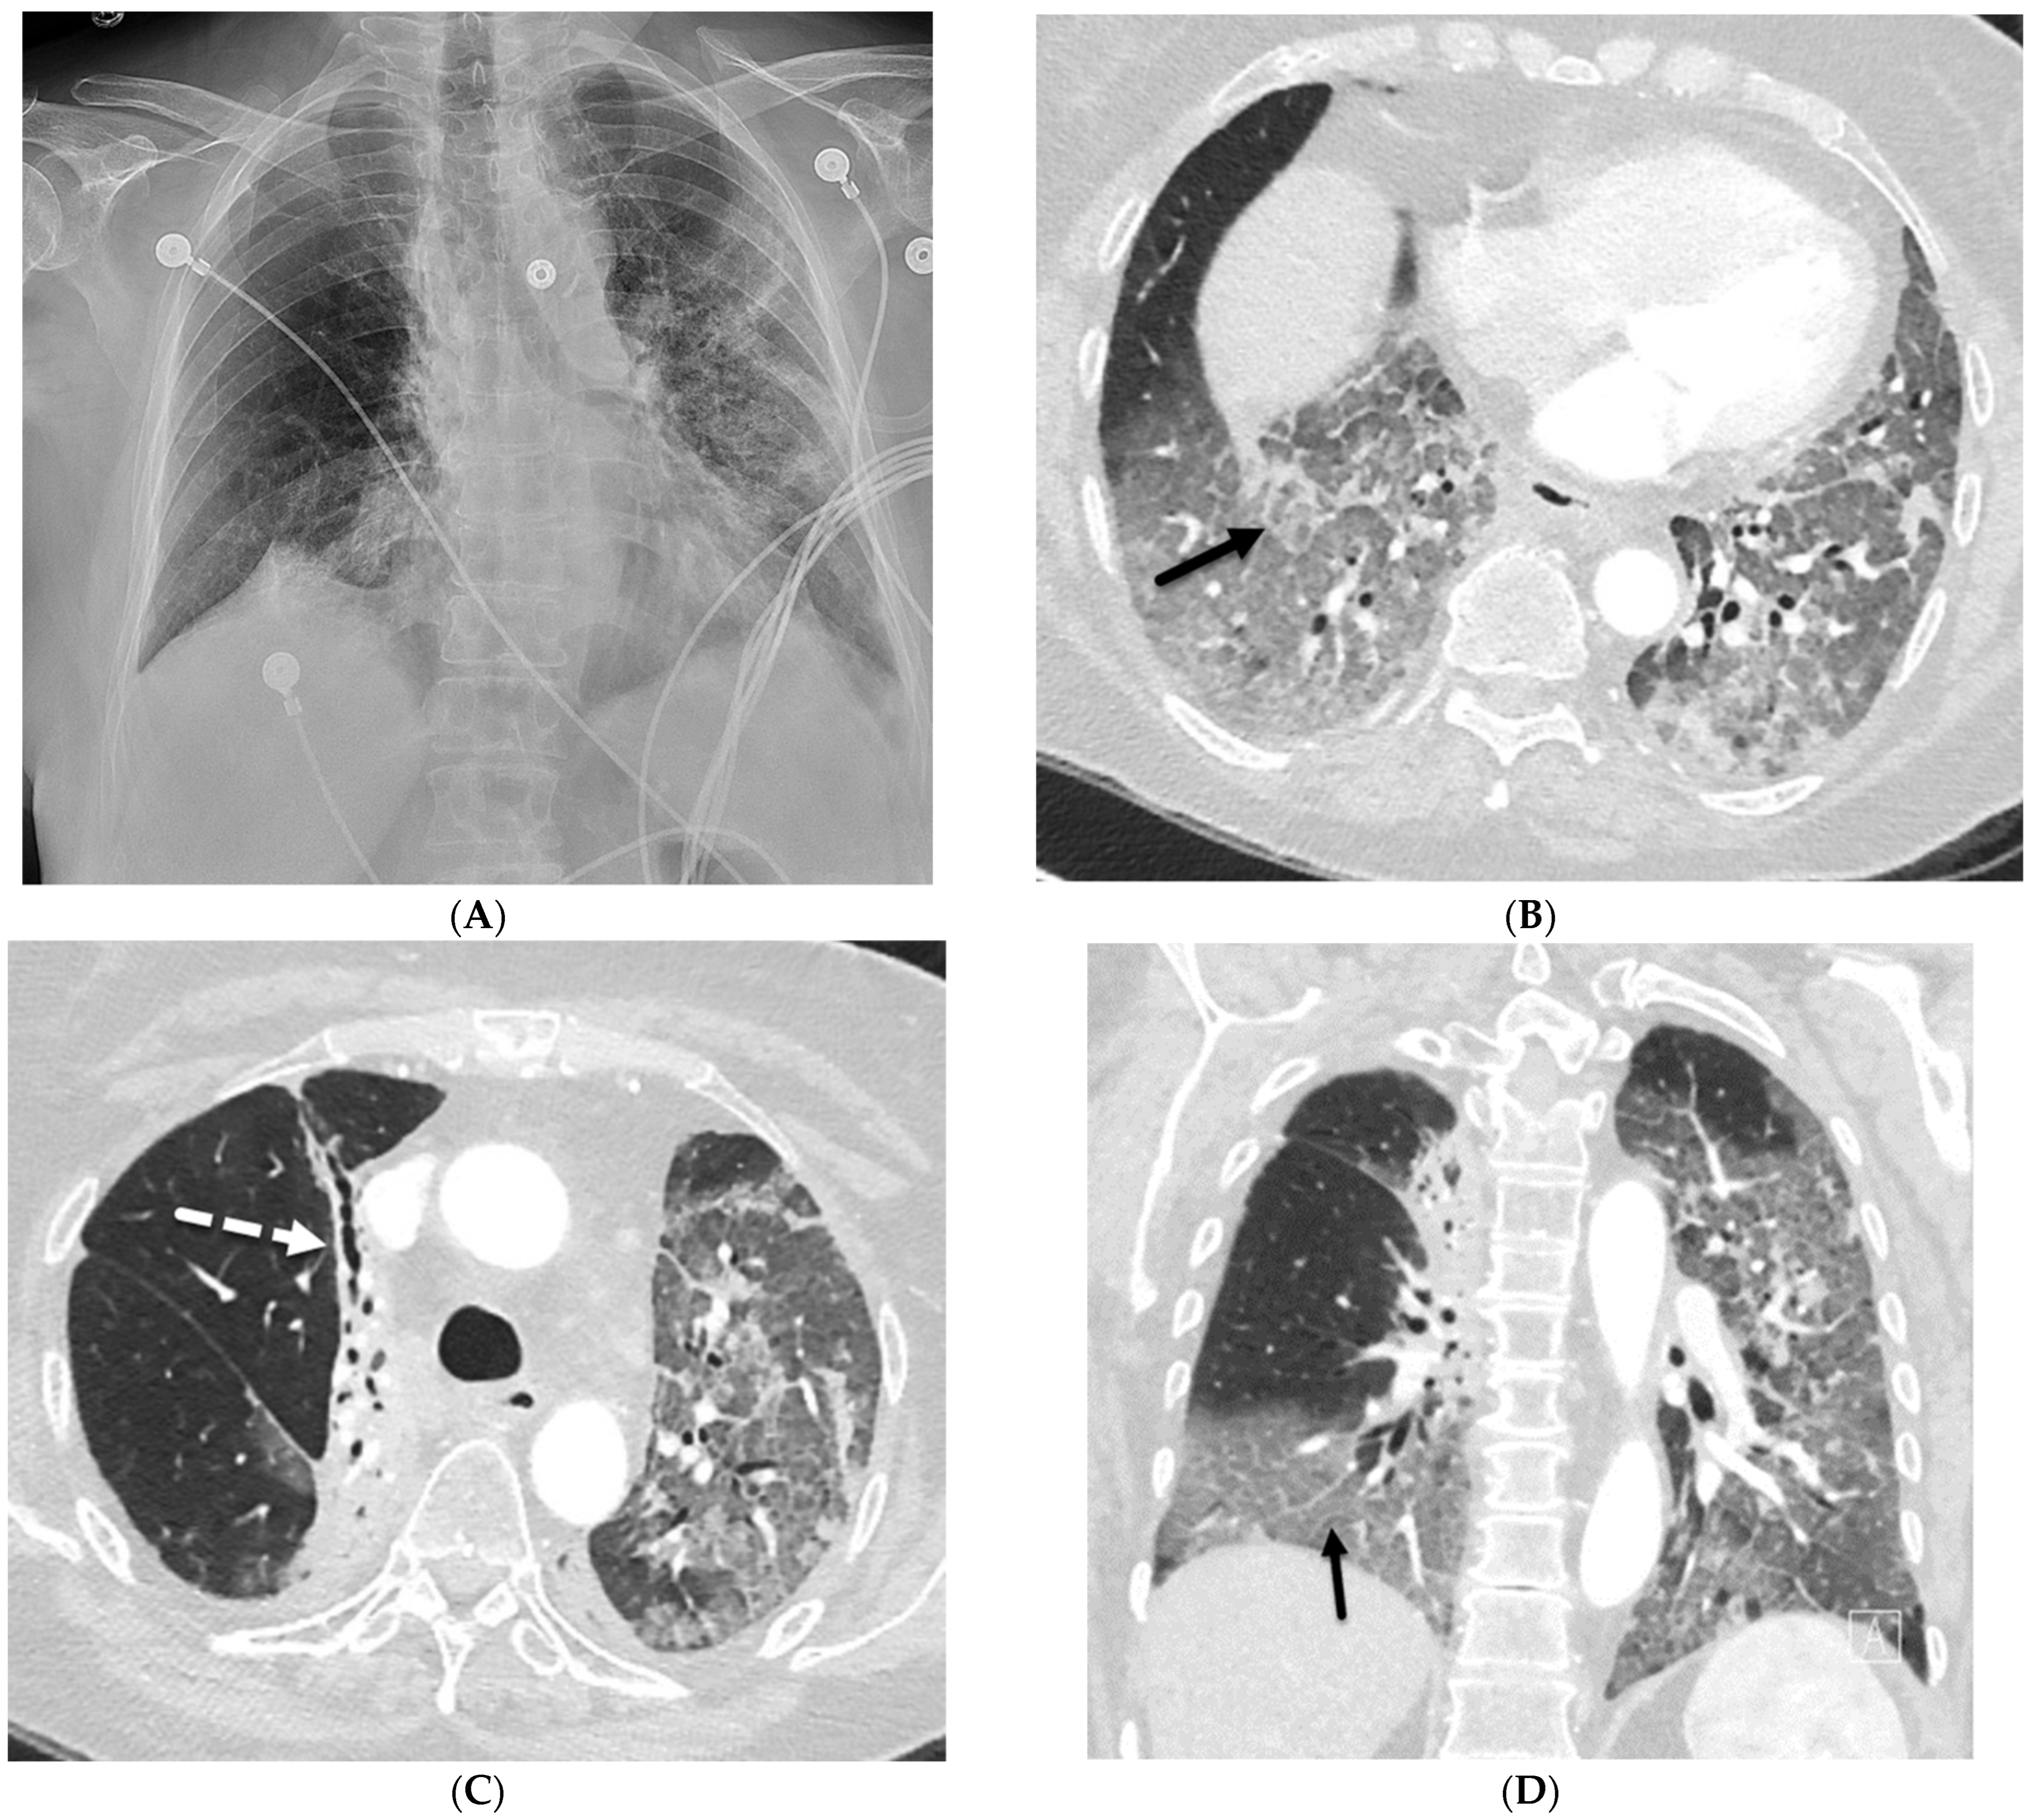

2.1. COVID-19 Pneumonia

2.2. Bacterial Pneumonia

2.4. Pneumocystis Jiroveci Pneumonia (PJP)